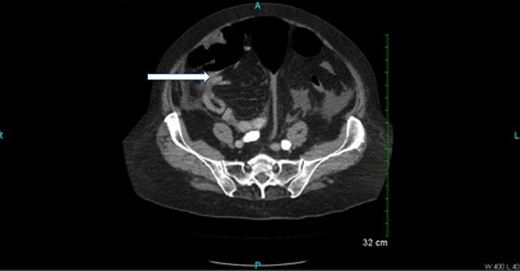

CT scan (Figs 2 and 3) revealed a large hematoma at the lateral margin of the spleen that displaced the spleen medially and compresses its lateral margin. A moderate amount of relatively low attenuation fluid also tracked into the right paracolic gutter and perihepatic space. There also appeared to be a 3.5 × 2.5 cm broad-based mass along the wall of the right colon. The CT scan of the chest also demonstrated a pulmonary embolus in a subsegmental artery of the right upper lobe. Given these findings, the patient was aggressively resuscitated with packed red blood cells and taken emergently to the operating theatre.

Oral and intravenous contrast-enhanced CT of the abdomen demonstrating air within the colonic lumen and a large haematoma at the lateral margin of the spleen that displaced the spleen medially, compressing its lateral margin. A moderate amount of relatively low attenuation fluid is also seen tracking into the right paracolic gutter and perihepatic space.